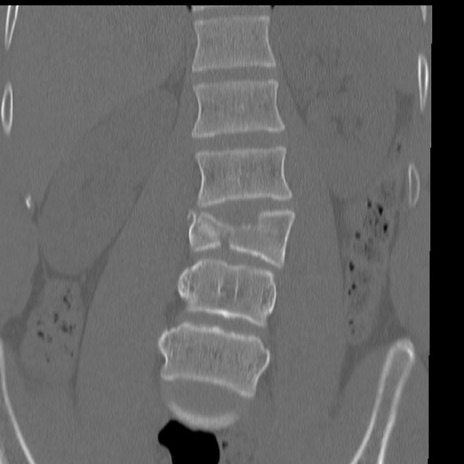

症例3 腰椎CT(冠状断像)

腰椎CT

矢状断像